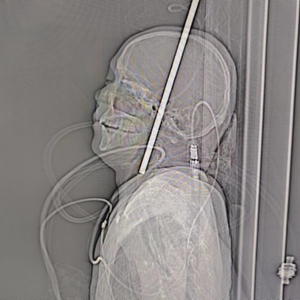

“节假日惊险病例:一根钢筋穿颅而过,小伙子竟然顶着钢筋自己走到医院急诊,我们都惊呆了……”

国庆假期伊始,浙江大学医学院附属第二医院(以下简称浙大二院)急诊科副主任医师卢骁在社交媒体发了一条消息,迅速引起网友围观。从其分享信息看,钢筋从患者头顶贯通到下颚,差一点就要穿出颈部。

随后,他被转至浙大二院。抵达时,距离意外发生已有3小时左右。卢骁回忆,初见A先生时,裸露在外的钢筋仍有数十厘米,如成人食指般粗细。

巨大的金属异物扎进脑子,伤者还能自行去医院、经历几个小时仍保持清醒,卢骁坦言非常罕见。

前述《中国法医学杂志》分析,这可能源于几方面原因。包括贯穿颅脑的钢筋经过大脑“哑区”,伤后不显示明显的神经系统体征。其次,贯穿颅脑的钢筋是比较光滑、粗细均匀的异物,被颅骨固定、压迫创周血管,明显减缓颅内出血速度和出血量。

到院几分钟后,A先生从神志恍惚转而昏迷。“能活着送过来,说明没有伤及脑干等重要脑组织,未影响其重要的神经中枢;也没有伤及颈动脉、颅内大血管,未造成致死性大出血。真是不幸中之万幸。昏迷是因为脑内出血量增加、颅内压过高导致脑疝,需要尽快急诊手术。”卢骁告诉“医学界”。